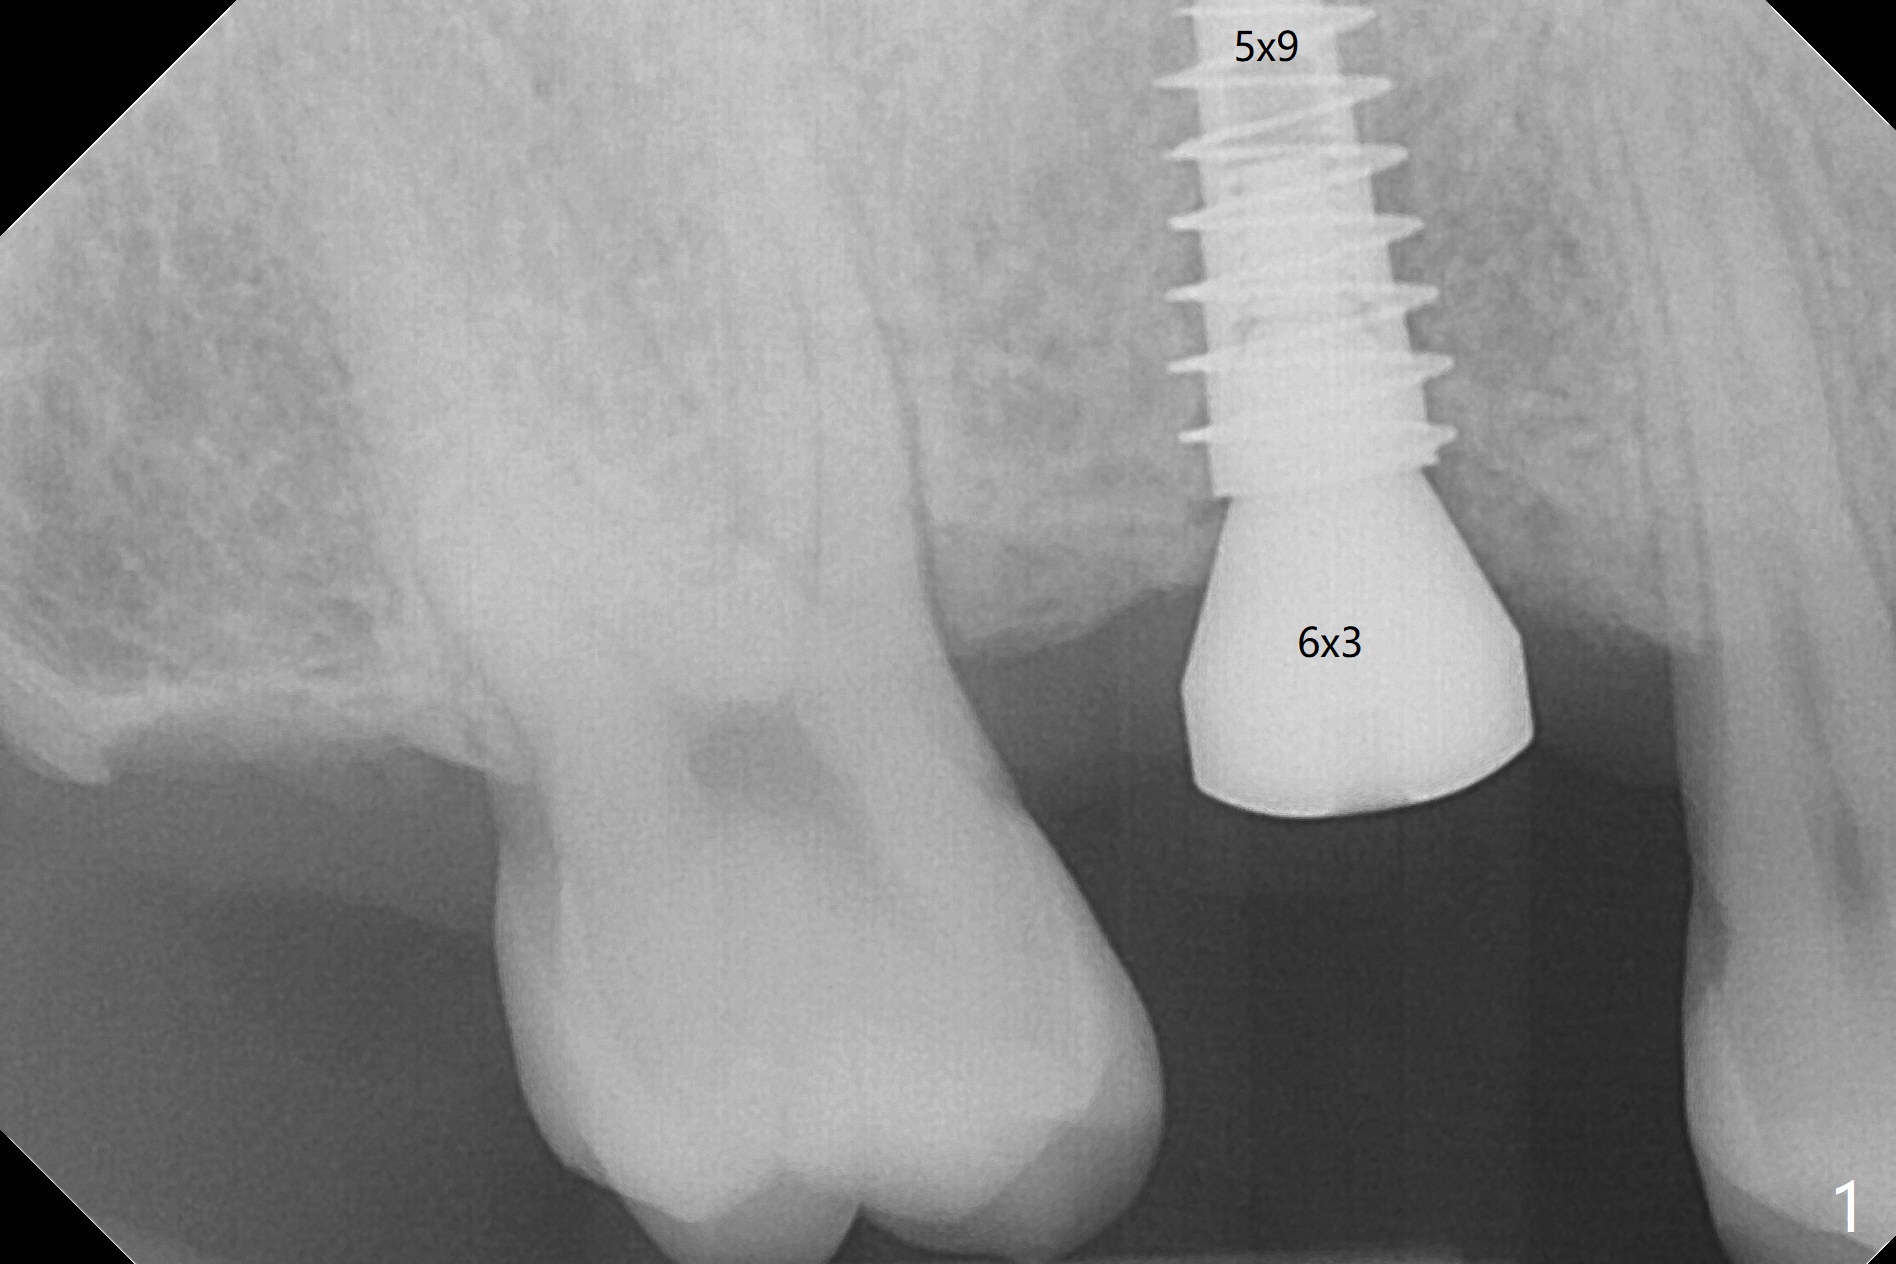

由于冠状病毒流行,右上六种植推迟七个月。老导板用起来好像挺顺手,植体位置仿佛正常(图一)。使用6毫米profile钻头后,放置6x3毫米愈合基台。术后5.5个月放置修复基台(图二),基台直径再小一号,放置就可能容易些,容易就位。